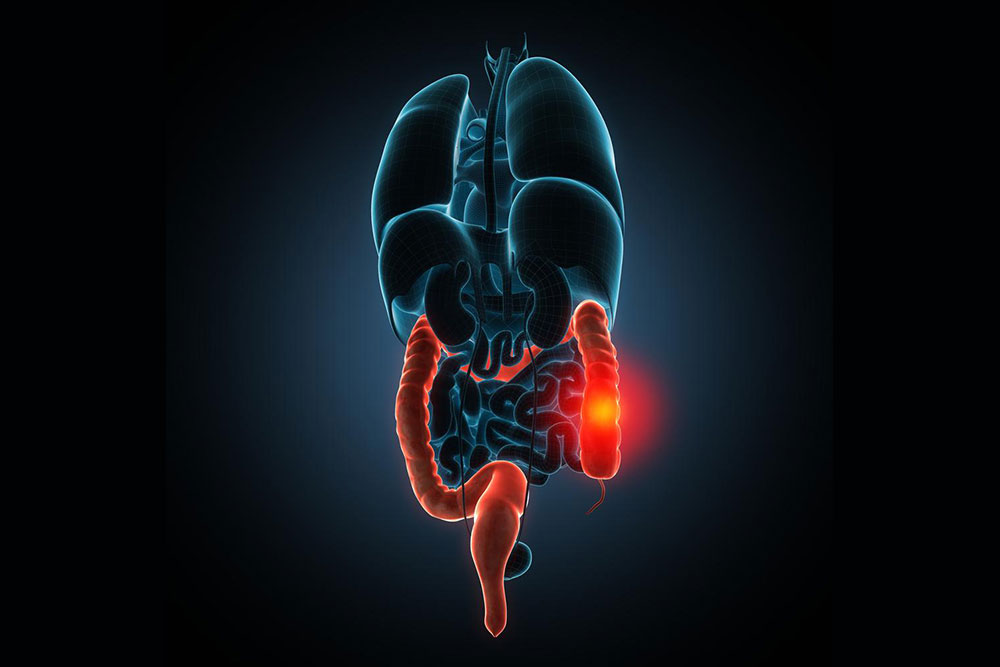

Ulcerative colitis disturbs the colon of the human body. The colon is a part of the digestive system and hence once colitis affects the colon, it tends to distress the digestive system as well. There can be a lot of many health issues that directly hamper the digestive system and therefore we are unable to identify whether or not the issue is caused by Ulcerative colitis.

Ulcerative colitis has different severity levels and this depends on which part of the colon is affected by colitis. Also, there are cases wherein the colitis symptoms might first appear and then disappear. For instance, a person might not experience any sign or symptom of colitis for weeks and then suddenly after a few months, these might come back.